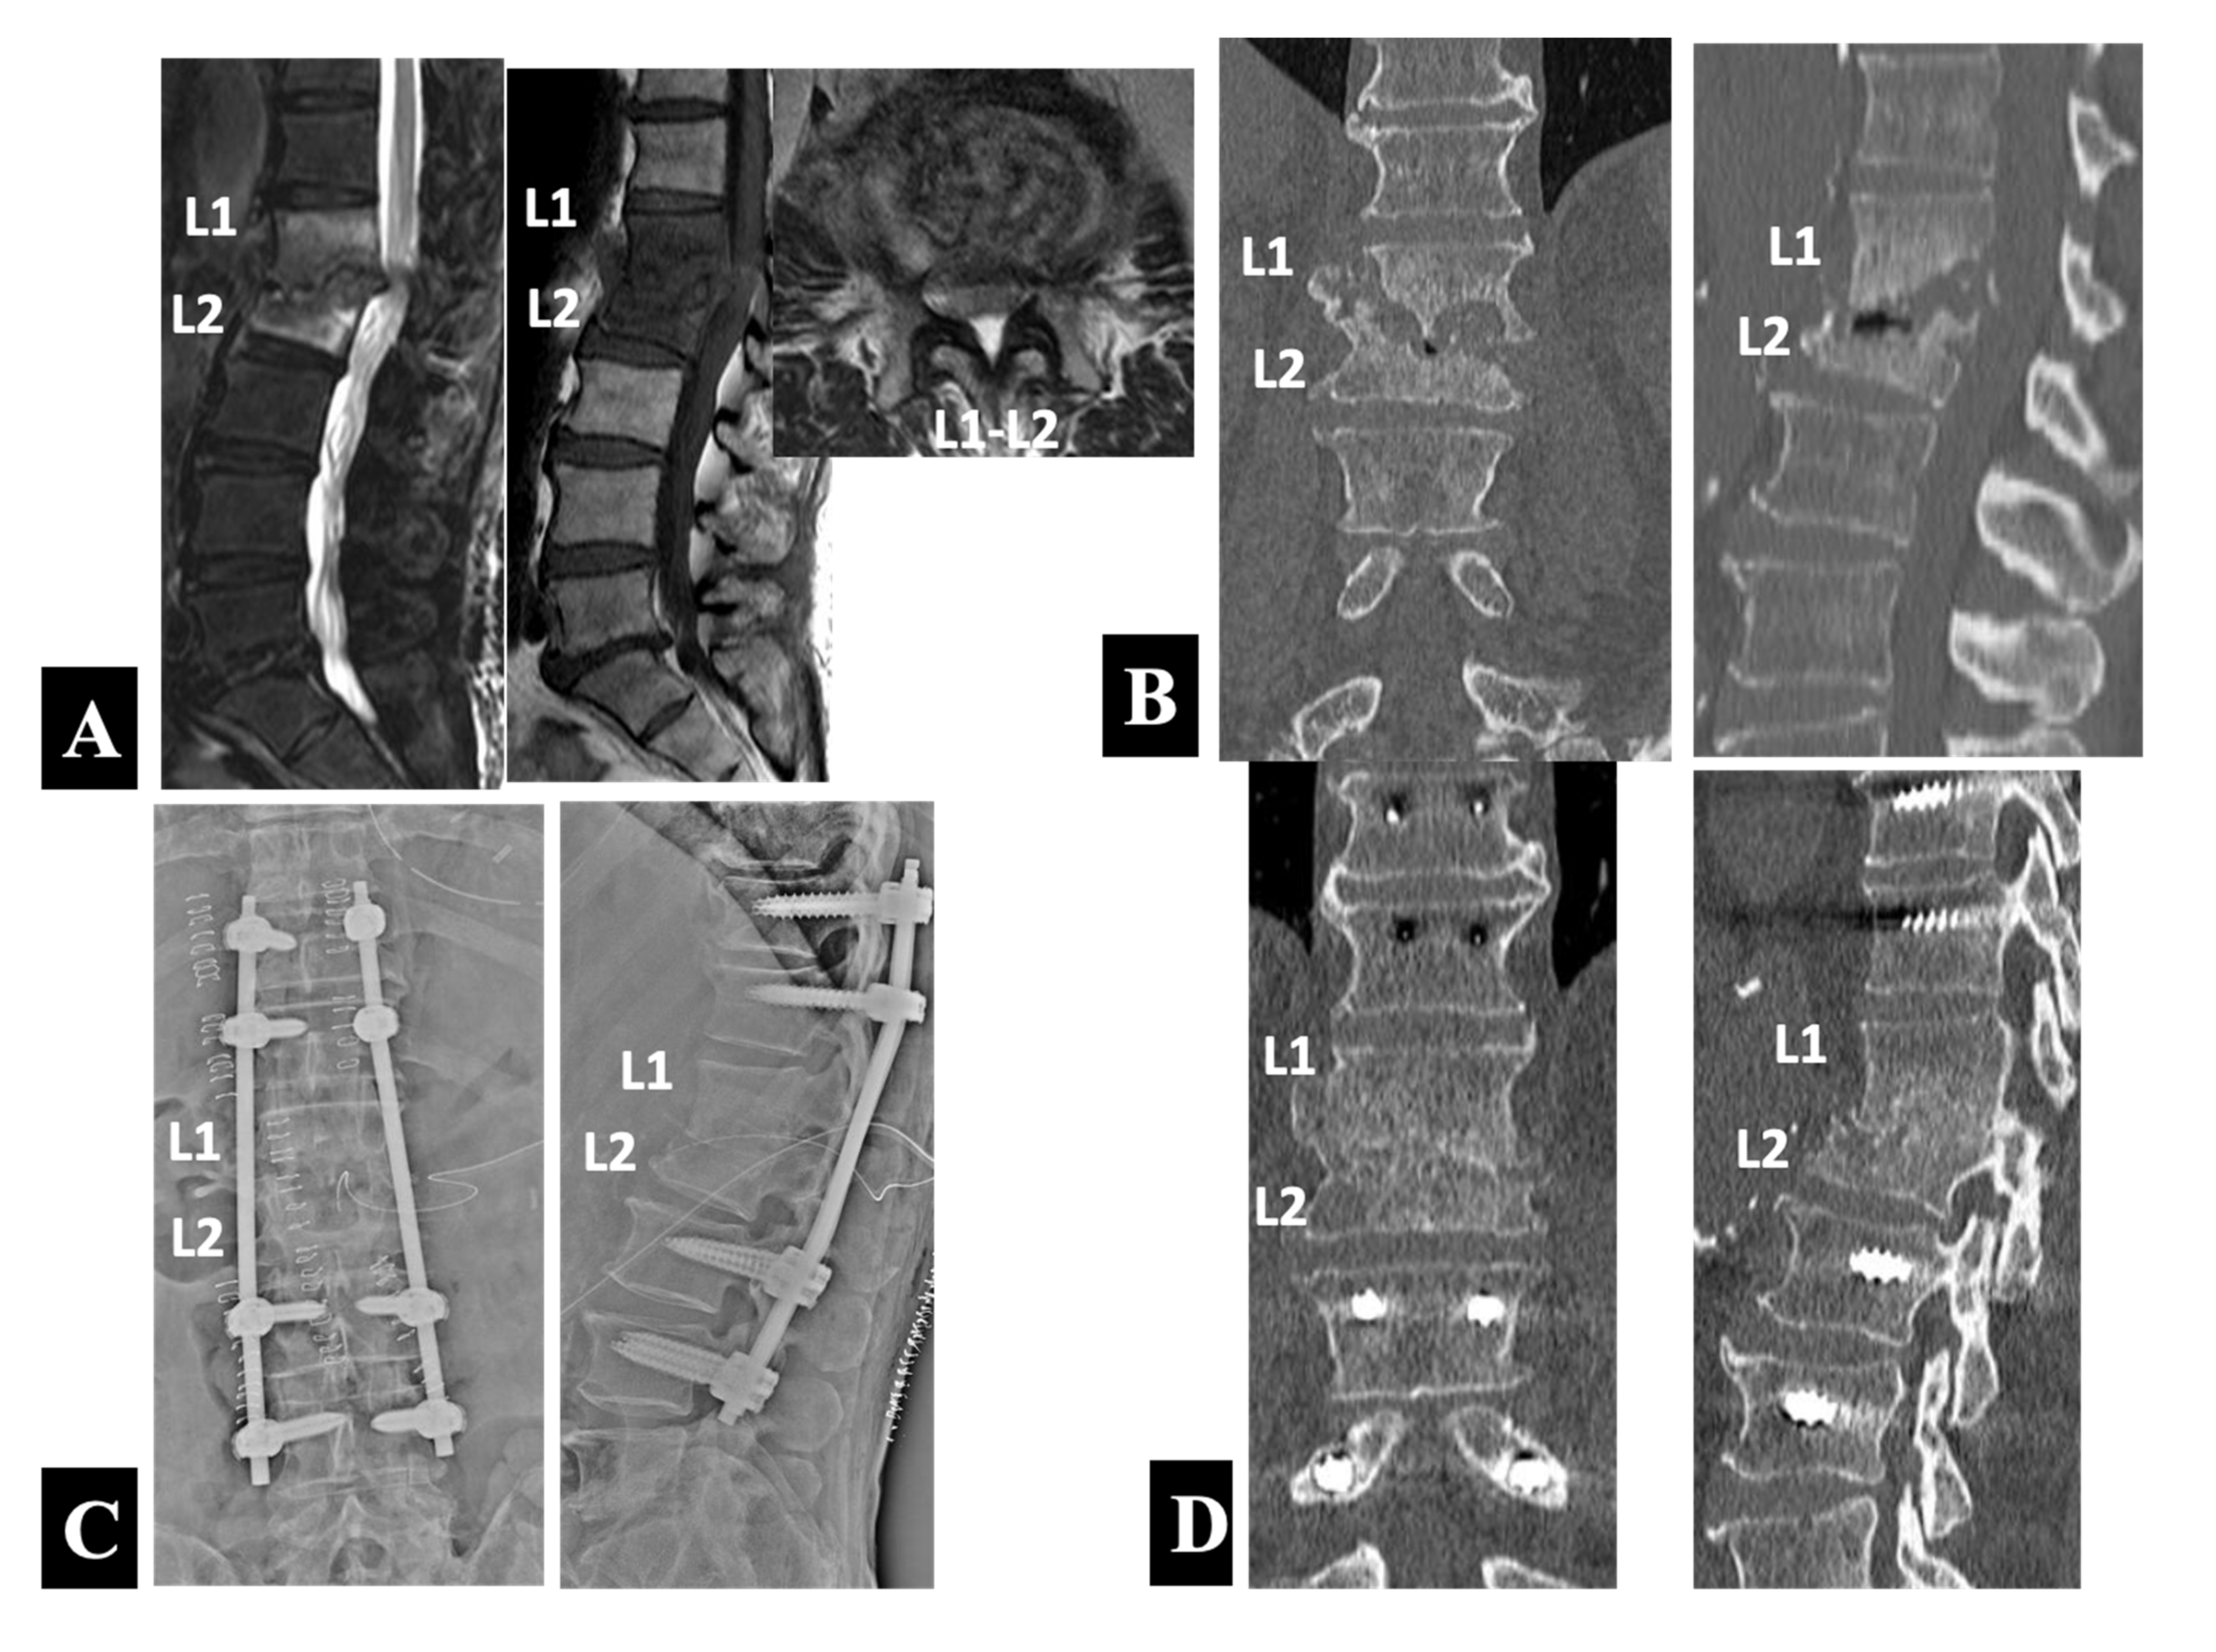

Figure 4. Preoperative sagittal T2- and sagittal and axial T1-weighted MRIs (A) and coronal and sagittal reformatted CT images (B) in a 77 year old neurologically compromised man with relapsed pyogenic spondylodiscitis at L1 and L2. He underwent a single-stage operation with PPS–rod fixation at the unaffected vertebrae of the T11 and T12 rostrally and the L3 and L4 caudally followed by posterior exposure for decompression and debridement at L1–L2 (Group 2-A) as shown by postoperative anteroposterior and lateral plain radiographs taken immediately after surgery (C) and coronal and sagittal reformatted CT images 1 year postoperatively (D).

A 77 year old man suffered from a relapse of spinal infection, presenting with lower back pain and bilateral lower limb weakness after six months of conservative treatment with a culture-negative result in the CT-guided biopsy. The antibiotic regimen consisted of 4 weeks of intravenous linezolid administration and subsequent oral use of rifampicin in combination with trimethoprim/sulfamethoxazole (TMP/SMX). He had comorbid illnesses such as diabetes mellitus and atrial fibrillation. The MRI scans (Figure 4A) showed typical findings of spondylodiscitis with high-intensity T2 and low-intensity T1 signals of the L1 and L2 vertebral bodies and loss of definition of the endplates. An abscess and/or inflammatory tissues formed in the anterior epidural space with spinal cord compression explained neurological symptoms and signs of the patient. The CT scans (Figure 4B) demonstrated severe destruction of the L1 and L2 vertebral bodies with local kyphosis.

Because of the presence of neurologic compromise, he underwent a single-stage operation with PPS–rod fixation followed by posterior exposure for decompression and debridement at L1–L2. Postoperative radiographs (Figure 4C) showed the posterior instrumentation construct with the PPSs placed into the unaffected vertebrae of the T11 and T12 rostrally and the L3 and L4 caudally. The CT scans 1 year postoperatively and immediately before the implant removal (Figure 4D) revealed bone union at the affected L1–L2 intervertebral level.